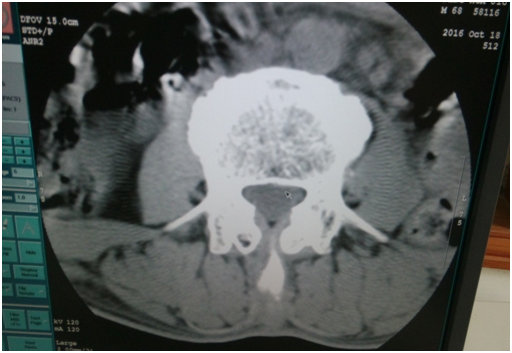

這是當天做完這個圖像后,機器出現無法曝光。

2.     我用頭部條件掃水膜,可以曝光。但出來的圖像有環狀偽影,需要做校正。但是雙排的水膜在老區,只能第二天再做校正。第二天做病人,做頭部的都還行,但是做腰椎圖像出來條紋狀偽影。

更換電源后,做校正。條紋狀偽影沒有了。

但是環狀偽影還是有??紤]到可能之前的校正文件有問題,做restore,導入之前好的校正文件。重新做校正,之后掃水膜圖像有明顯改善。